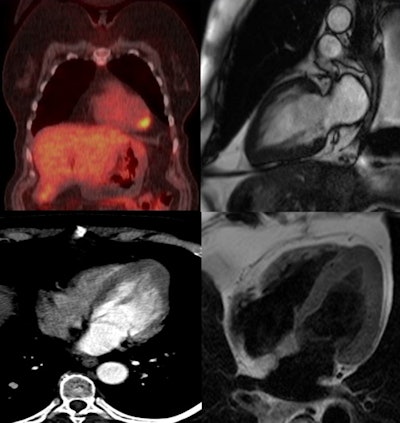

Whole-body PET/CT (top left) shows lung cancer and FDG avidity at the left ventricular apex. Image courtesy of Dr. Esin Gezmis.Also resulting in cardiac FDG activity are inflammatory lesions like myocarditis, which tends to show regional uptake, and endocarditis, in which avidity at the valves is seen. Focal FDG uptake can also be observed due to cardiac involvement of sarcoidosis, particularly in the acute inflammatory stage, but it is difficult to differentiate it from cardiac neoplasms and metastasis, according to Gezmis.

At the Milan meeting, Gezmis reported about the case of a lung cancer patient with focal cardiac FDG uptake on whole-body oncological PET/CT, which turned out to reflect apical HCM when further evaluated with CMR.

A subsequent whole-body FDG-PET/CT scan showed uptake in the mass and right hilar lymph node, confirming the diagnosis, but increased focal activity was also noted at the apex of the left ventricle, which appeared to be within the wall rather than the lumen. This raised the possibility of cardiac metastasis, which would have changed the management of the patient, and further evaluation was required.

Despite the fact it was not ECG-gated, the thoracic CT scan was reassessed regarding the heart by putting the images into true cardiac planes using multiplanar reconstruction. This demonstrated the loss of tapering of myocardium from the base to the apex with thickening of distal walls, suggesting apical HCM.

Contrast-enhanced cardiac MRI was performed to rule out metastasis and validate the apical HCM diagnosis. The images showed disproportionate and focal wall thickening in the left ventricular apex, which corresponded with the area of avidity on the PET/CT scan. There was also a "spade-like" configuration of the apical left ventricular cavity, and contractility of myocardium was preserved.

"No mass or gadolinium enhancement was noted and the appearance was in keeping with an apical hypertrophic cardiomyopathy phenotype. The pathology test results from the CT-guided biopsy of the lung mass and subsequently performed right lower lobectomy were adenocarcinoma. The benefit of chemotherapy was outweighed by risk and the patient has been under follow-up since then," Gezmis concluded.